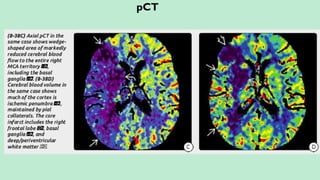

pCT

pCT inVarious Areas of Brain: MTT:

Grey Matter (BG and Cortex) – Red/Yellow. Slow – Red.

White Matter – Blue. Normal – Blue.

Ischemia – Blue/Purple and Infarct/CSF – Black.

Infarct Core (Irreversibly Damaged Brain):

a. Matched Perfusion (CBV and CBF – both decrease).

b. Increased MTT.

Ischemic Penumbra:

c. Perfusion Mismatch (Normal CBV, decreased CBF).

Penumbra = CBV – CBF.

Prolonged MTT (145%) beyond infarct core i.e. CBV/MTT mismatch = Penumbra.

FLAIR – DWI Mismatch = Penumbra.